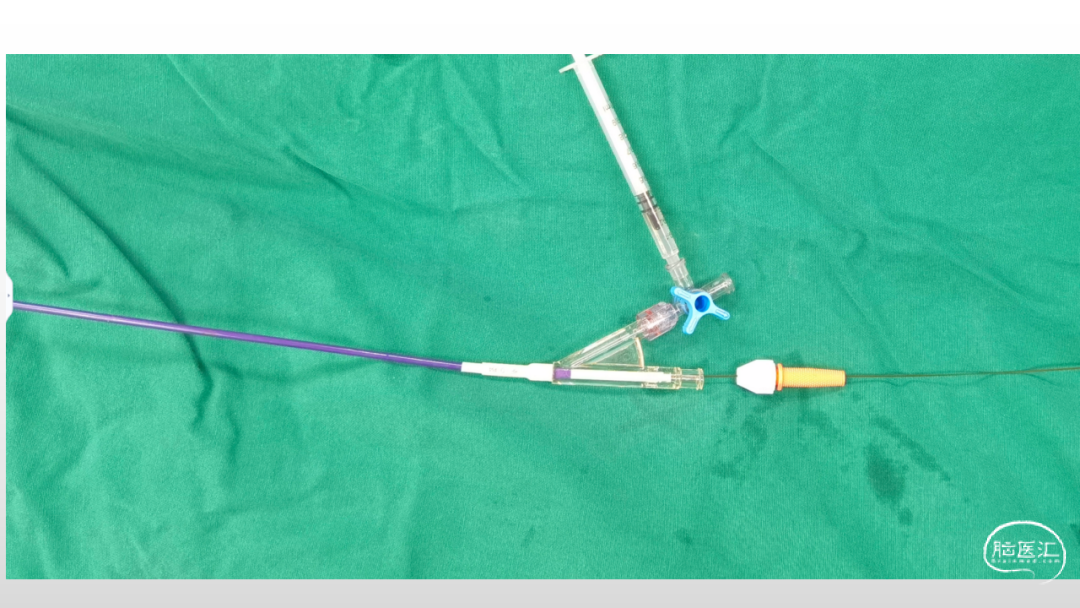

取之有道·第54期|李子付:Flowgate2取栓应用